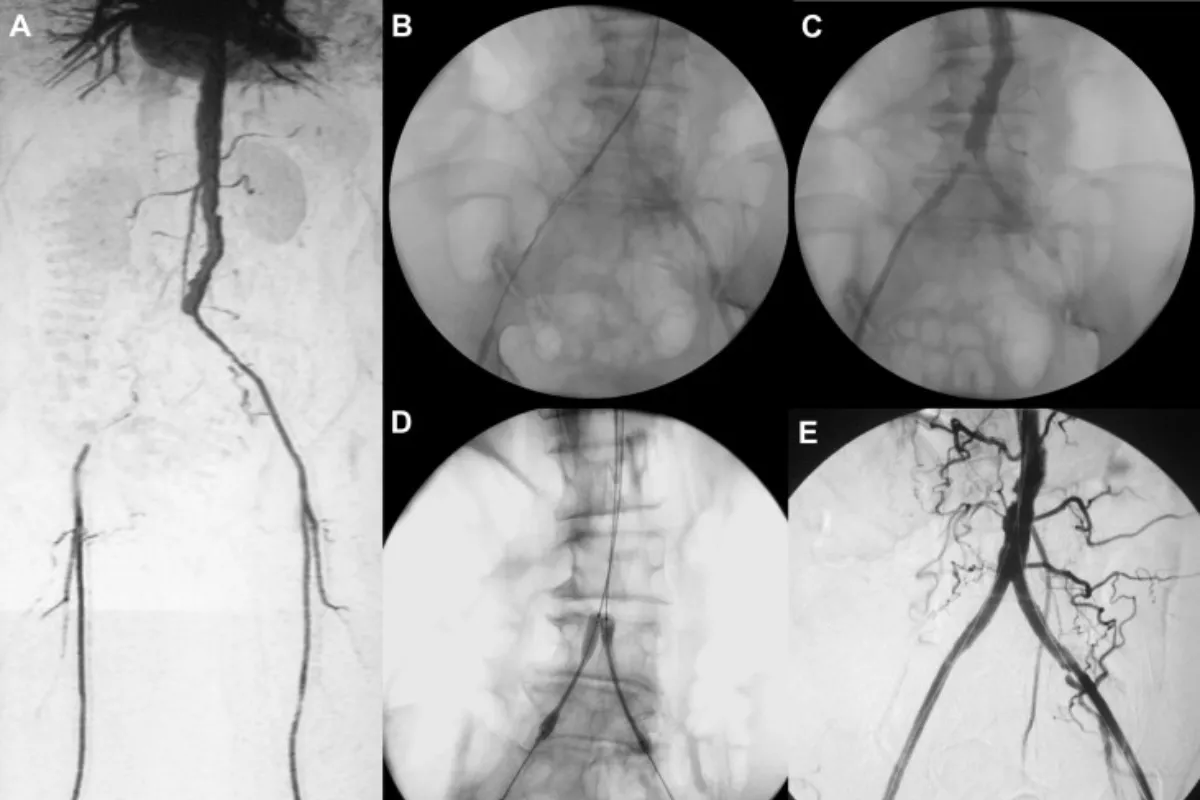

Peripheral Angioplasty procedure at Sarda Vascular Centre Dehradun

Interventional Radiology (IR) uses real-time imaging such as X-ray, ultrasound, CT, or MRI to guide tiny instruments through the body for treatment — without large surgical incisions.